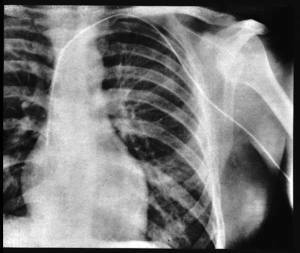

se observa la primera aplicación de rayos X por una fractura de brazo de un paciente la cual se lleva a cabo por médicos de Estados Unidos

se realiza una incisión en la vena cubital introduciendo un catéter urinario dentro de la aurícula derecha por parte de Forssman haciéndoselo así mismo, luego se toma una radiografía mostrando el procedimiento terminado.